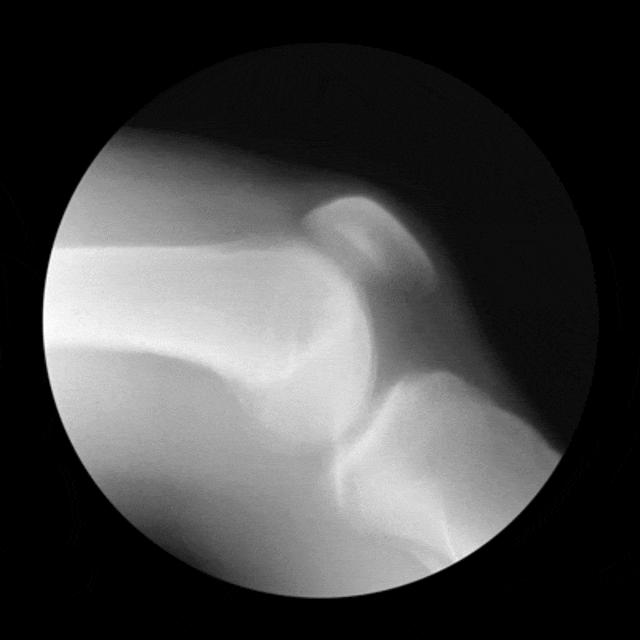

对膝关节来说,最好的检查方式是核磁共振,既可以看到关节里是否有积液,判断积液量多少,又能很好地评估膝关节内半月板、韧带和软骨的情况;如果发现半月板损伤,还可以对损伤进行分级。此外,膝关节的常用检查还有X片、CT、B超、穿刺检查等。

关节肿痛和功能受限为发作性,1~2年发作1次,不发作时无症状;X线无明显改变,或仅有轻度软骨下骨硬化。

疼痛与天气变化有明显关系;发作次数增加,症状进行性加重,1年发作2次以上;X线片上可见增生的骨赘,关节间隙出现狭窄。

这时期关节严重变形,出现“O”型腿和“X”型腿,疼痛剧烈,举步维艰;X线片可见关节周围有明显的骨赘形成,或可见游离体,关节间隙明显狭窄甚至消失。对此类患者保守治疗无效时,要积极考虑手术治疗。